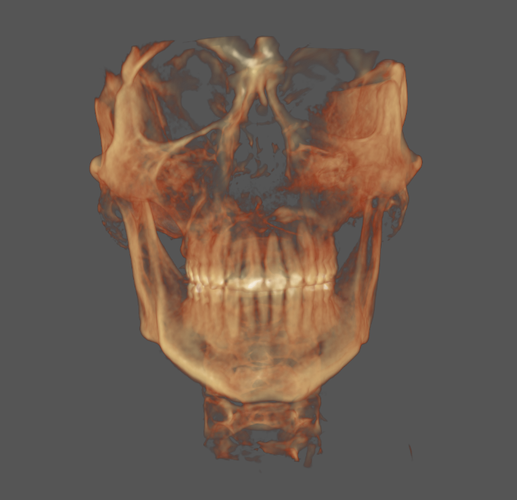

I'm currently 22 and have a recessed mandible, maxilla and narrow palate, all of these are not severe but add up, this has lead to mild sleep apnea, TMJ, and migraines.

I'm currently 22 and have a recessed mandible, maxilla and narrow palate, all of these are not severe but add up, this has lead to mild sleep apnea, TMJ, and migraines.